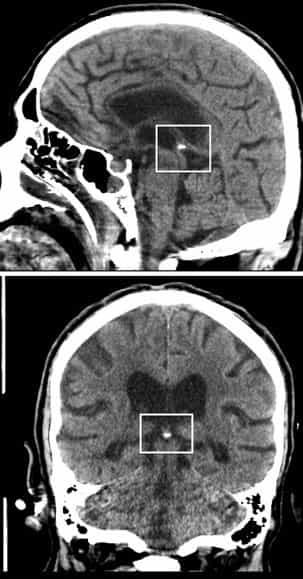

Our Approach to Fluoride: Informed Choices for Your HealthOne big concern is fluoride’s possible impact on the pineal gland, a small part of the brain that helps regulate sleep by producing melatonin. Some studies suggest fluoride can build up in this gland because it attracts calcium, leading to calcification (hardening with calcium deposits). This buildup might reduce melatonin levels and affect sleep quality, mood, focus, and even deeper cognitive functions—things like intuition, mental clarity, creativity, and what some people call “multidimensional cognition” (the ability to process information beyond everyday logic, such as heightened awareness, pattern recognition, or subtle perception).

In holistic and spiritual communities, the pineal gland is often linked to mediumship (the ability to sense or connect with non-physical energies or insights). When calcified, some believe it may dull this sensitivity, making it harder to access inner guidance, dreams, or intuitive states. While mainstream science focuses more on sleep and hormonal effects, many patients report feeling “clearer-headed” and more in tune after reducing fluoride exposure—especially those who value mental sharpness, spiritual awareness, or creative flow. |

The evidence isn’t fully conclusive—calcification also happens naturally with age—but for those exploring holistic wellness, avoiding unnecessary fluoride is a simple step toward protecting both body and mind.